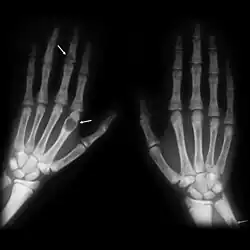

X-ray of two human hands, viewed with the palms facing downwards. Three light-gray malformations can be seen: one is present on the right-side of the right wrist, one is present three-quarters of the way up the middle finger of the left hand, and one is present in the first segment of the index finger of the left hand. White arrows have been added to the image to identify the tumors.

X-ray of the hands showing brown tumors in the long bones of the fingers

X-rays may also be used to diagnose the disease. Usually, these X-rays will show extremely thin bones, which are often bowed or fractured. However, such symptoms are also associated with other bone diseases, such as osteopenia or osteoporosis.[29] Generally, the first bones to show symptoms via X-ray are the fingers.[22] Furthermore, brown tumors, especially when manifested on facial bones, can be misdiagnosed as cancerous.[29] Radiographs distinctly show bone resorption and X-rays of the skull may depict an image often described as "ground glass" or "salt and pepper".[30][31] Dental X-rays may also be abnormal.[2]